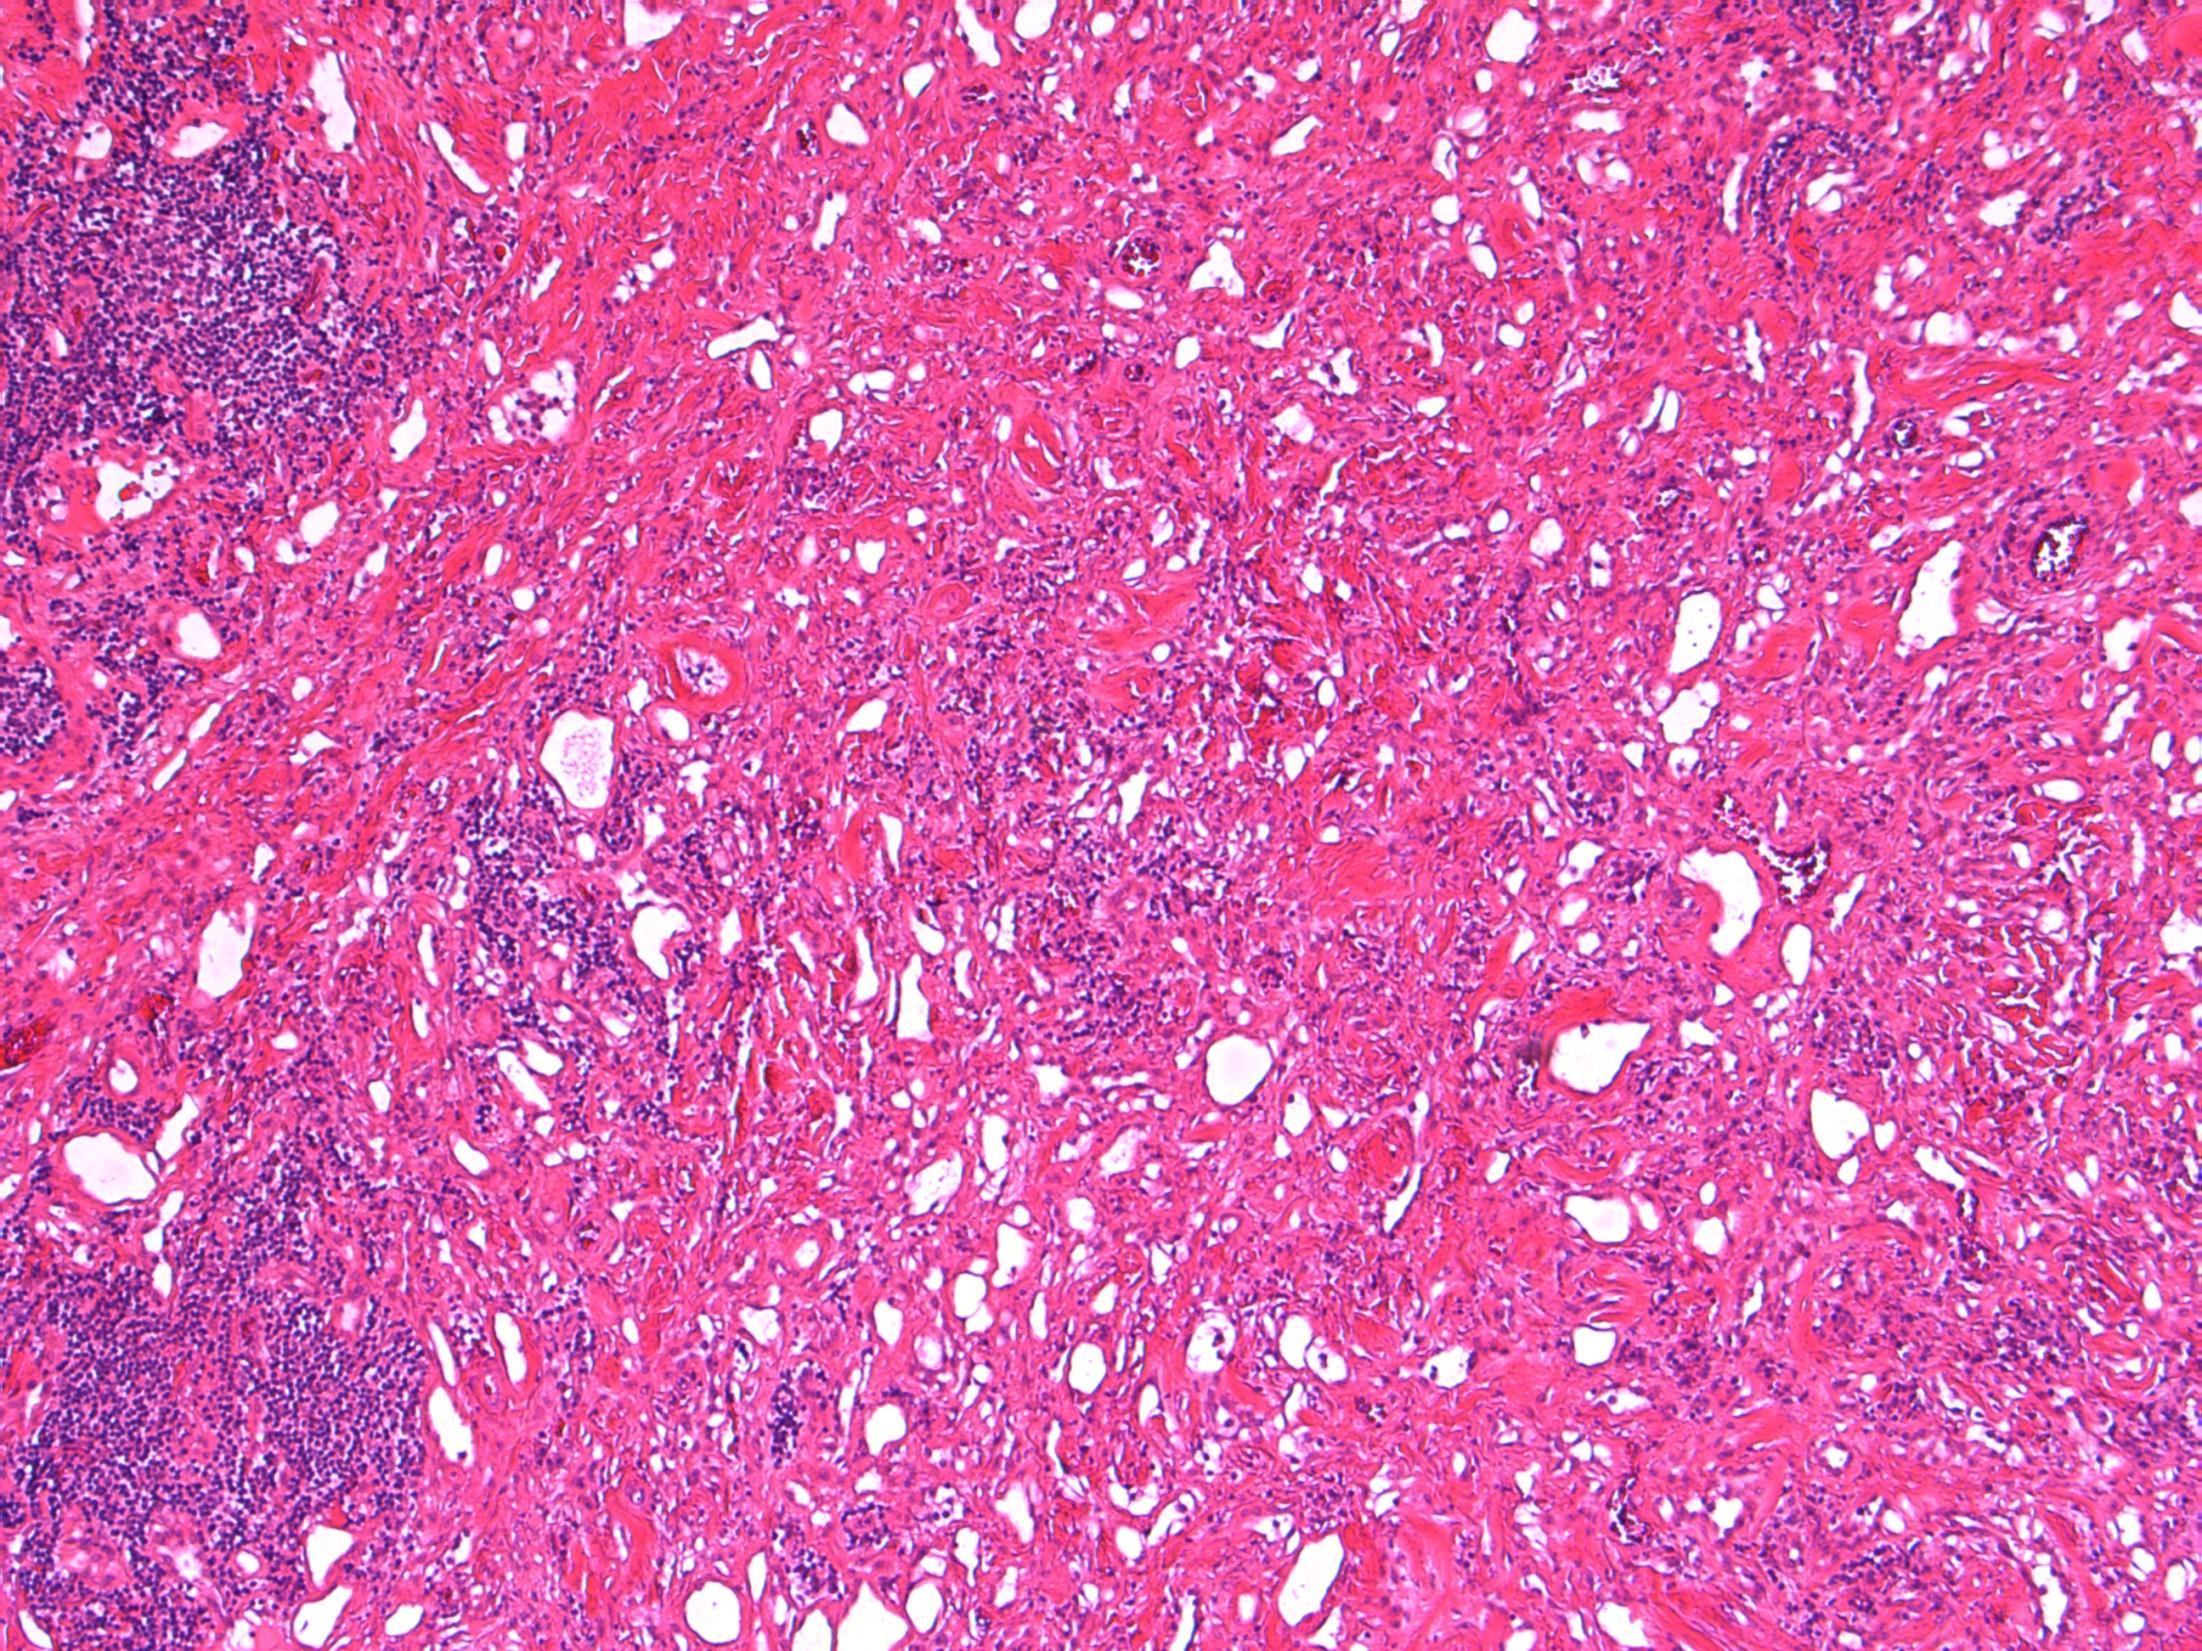

Liver - angiomyolipoma

Liver Description: Liver containing well circumscribed spindle cell tumour with 3 components – smooth muscle cells (predominant), adipose tissue and blood vessels. Diagnosis: angiomyolipoma Differential Diagnosis: Leiomyoma (usually no prominent vascular or adipose component, negative for HMB45) GIST (CD117+) Mets of sarcoma / spindle cell carcinoma – more atypia Plan: IHC: SMA+, HMB45+, CD117-, AE1/3+ Correlate with clinical history ? Tuberous sclerosis etc Comments: • Liver is 2nd commonest site after kidney • Often detected incidentally, usually benign • May be sporadic but is associated with tuberous

and with TSC2 / PKD1 contiguous gene

(especially if

AML

sclerosis

syndrome

bilateral/multifocal).

3.5 Clinical features, associations 3.0 Differential diagnosis and use of IHC 2.5 Description with diagnosis or DD including AML 2.0 Differential diagnosis with mention of AML but favouring other diagnosis 1.5 Differential diagnosis with no mention of AML or a benign diagnosis 1.0 Malignant diagnosis Case 14